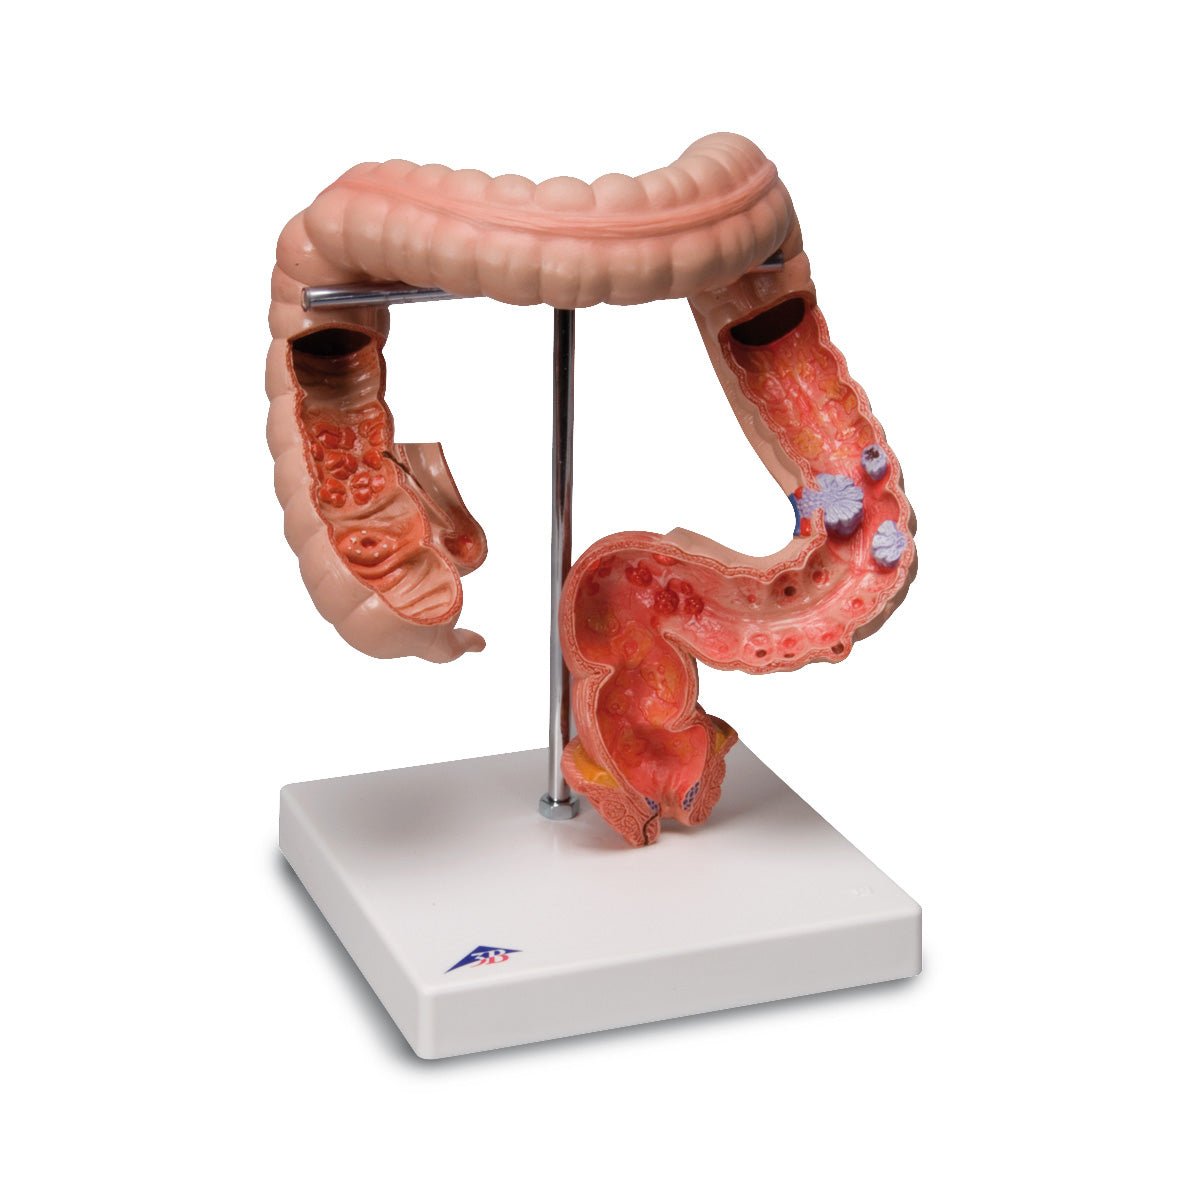

Anatomical models

Selling anatomical models is the mainstay of eAnatomi, although we also spend a lot of resources developing our own anatomical materials such as posters. Anatomical models are used for various purposes and can show both defined tissues, organs and organ systems. Are you looking for a simple model of bone tissue or perhaps an advanced torso model based on MRI technology, you can find it all at eanatomi.com.